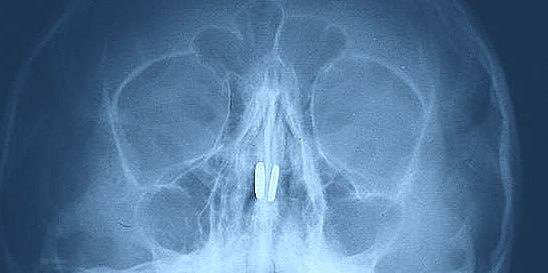

ЛОР-врач Валерия Наумова обнаружила по одному магниту в каждой ноздре мальчика. Игрушечные детали притянулись друг к другу через носовую перегородку, вызвав воспаление слизистой и сильный дискомфорт.

Специалистам удалось аккуратно извлечь инородные тела с помощью специального крючка. Перегородка носа не пострадала, а воспаление, по словам медиков, пройдет в ближайшее время без последствий.